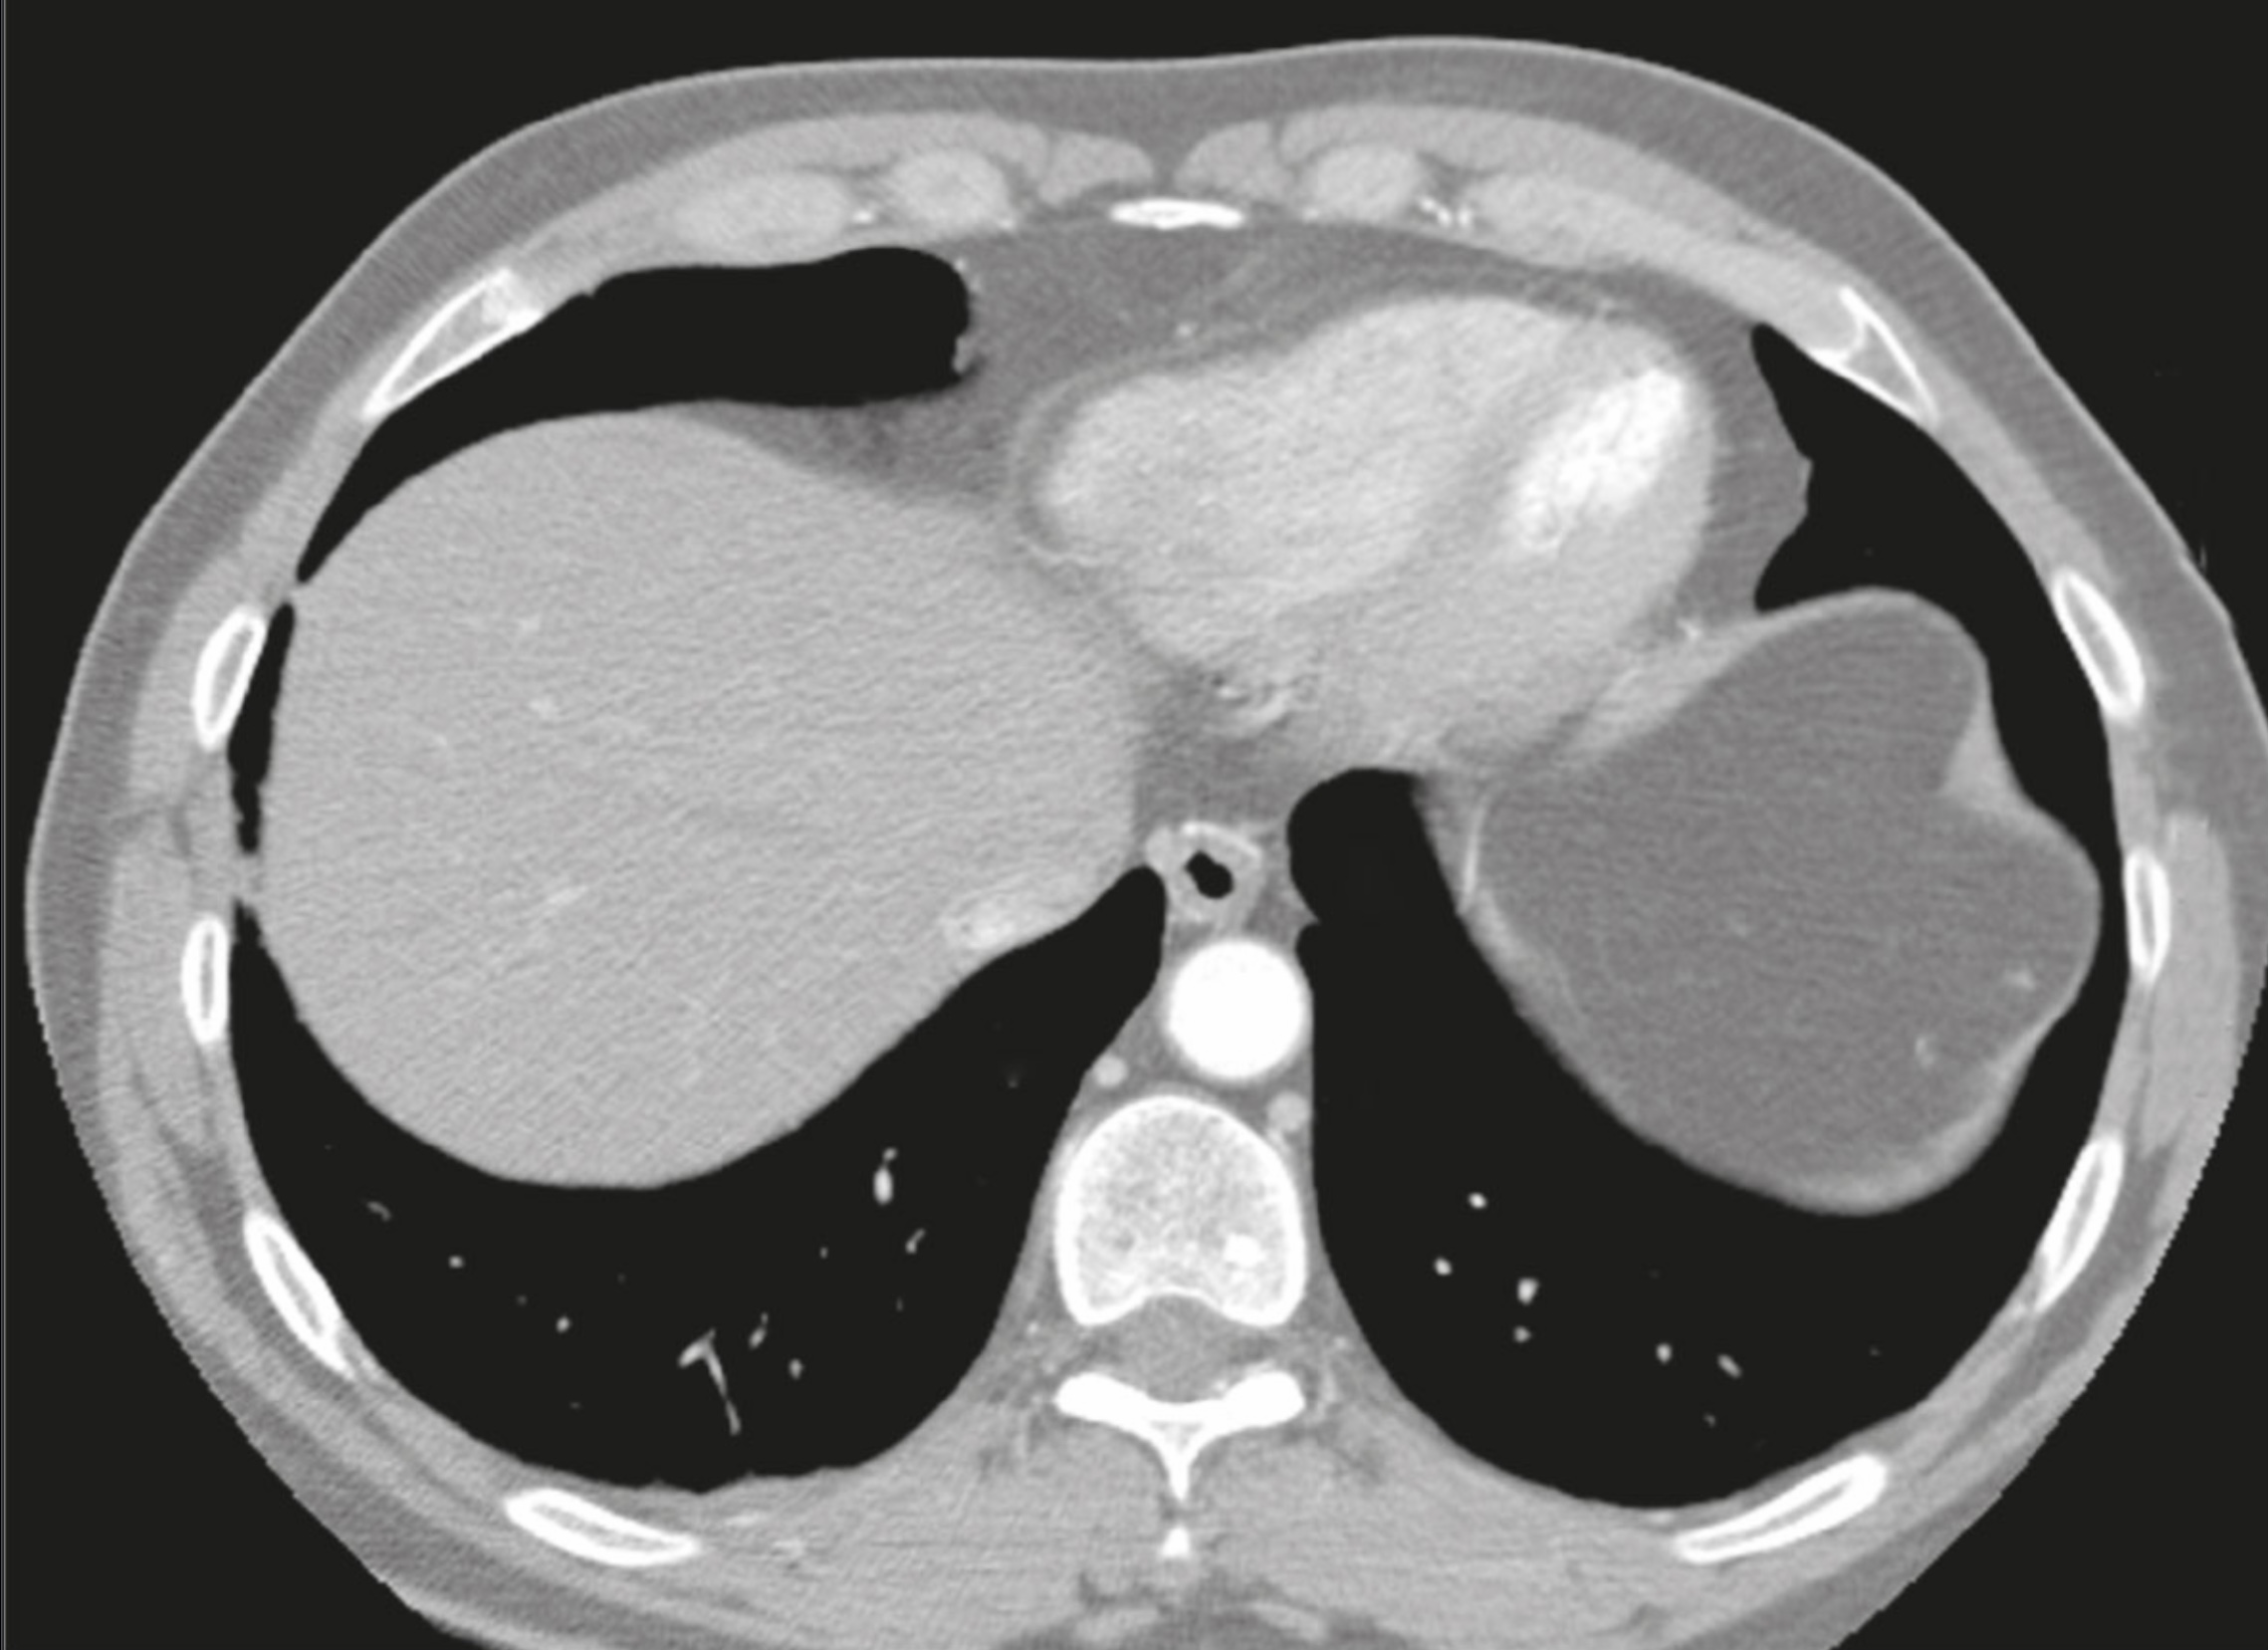

1. A 35 year old male presents to your clinic with cardiac tamponade after a car accident and you perform pericardiocentesis at the 5th-6th intercostal space. Discuss the anatomy of the pericardium, including attachments, stabilization, sinuses, relevant relationships, innervation, and blood supply. Describe the placement of the needle and the layers pierced during the pericardiocentesis procedure.

2. A 65 year old male presents to your clinic complaining of severe chest pain that radiates to his medial arm, and is diagnosed with a myocardial infarction, treated with coronary artery bypass surgery. During the surgery, clamping of the aorta and pulmonary trunk is performed at the transverse pericardial sinus. Describe the development of the pericardial cavity and pericardial sinuses. Include boundaries of the middle mediastinum and relevant developmental events, including germ layer derivatives. Explain the innervation to the layers of serous and fibrous pericardium and how the descent of the heart during development contributes to the location of these nerves in the thoracic cavity. Explain the location of the patient’s referred pain.